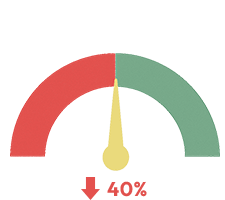

It also helped lower the hunger hormone ghrelin by up to 40%.

Meaning people ate less...

- Without even thinking about it.

- Without restriction.

- And without rebound.